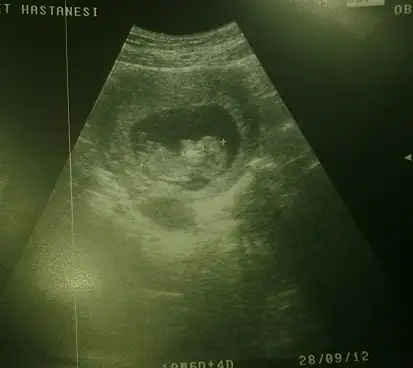

buda benım fındık kurdumun resmı ama ultrasonunu hıç begenmedık eşimle oyuzden hastanemızı ve drumuzu degıştırdık

Eki Görüntüle 368143

Eki Görüntüle 368144

41 kere maşallahhh